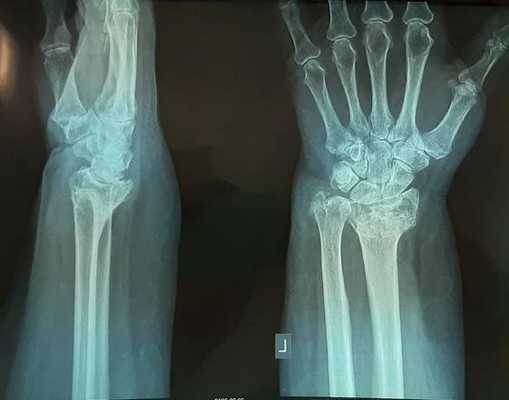

Рис. 3. Рентгенограмма кистевого сустава через 5 месяцев после травмы: имеется внутрисуставное смещение, деформация сустава.

Несмотря на это многие травматологи продолжают лечить такие переломы методом гипсовой иммобилизации. В конечном итоге перелом срастается с грубым смещением, суставная поверхность оказывается развёрнута в тыльную и лучевую сторону.

Формируется грубый артроз лучезапястного сустава. Клинически это проявляется визуально деформацией в области лучезапястного сустава, ограничением амплитуды движений, болью при физической нагрузке.